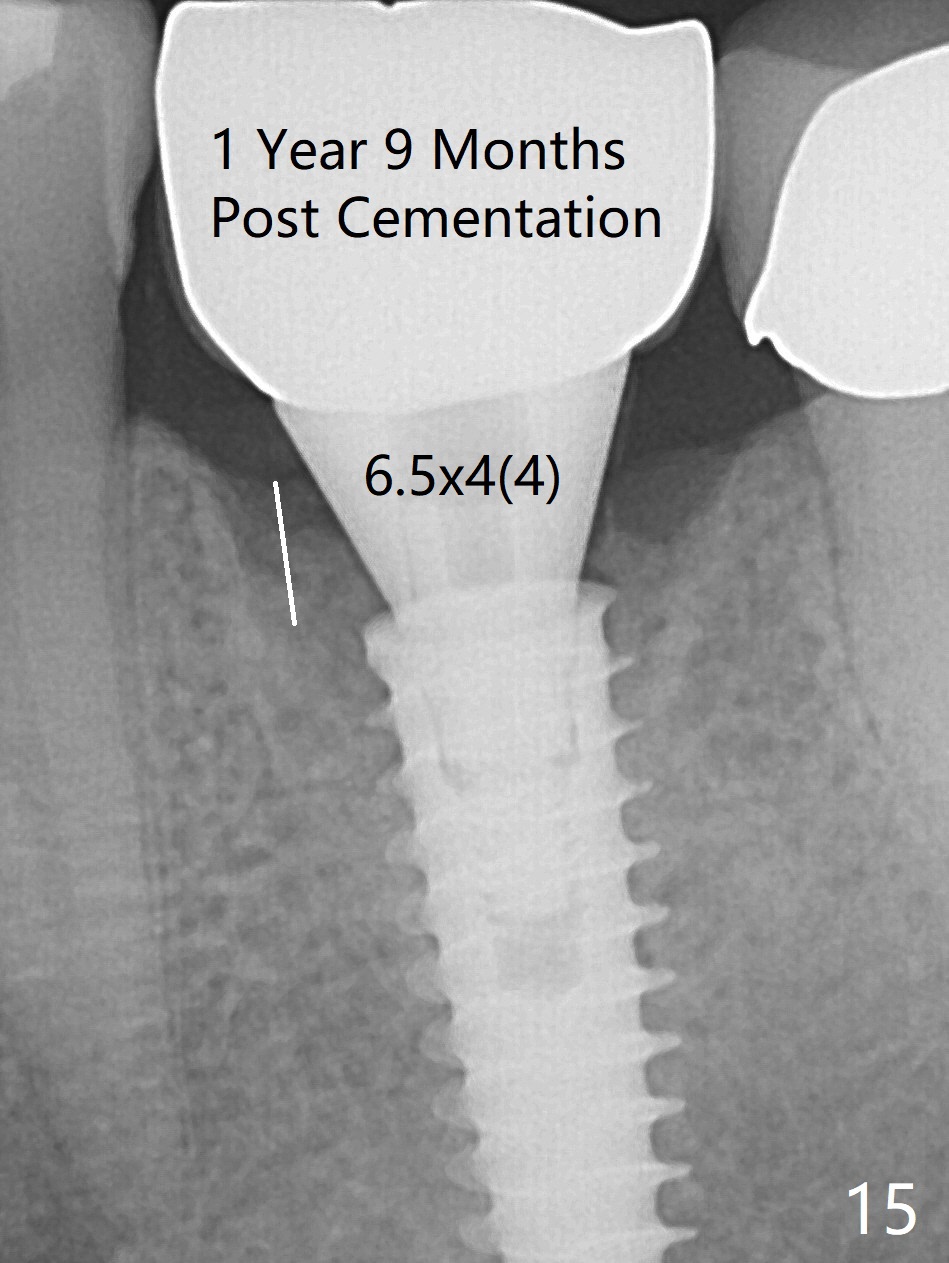

The gingiva looks healthy 8 months postop (3 months post cementation (after abutment screw retightening and addition of porcelain to proximal surfaces, Fig.12). New bone has apparently covered the implant plateau (Fig.13 arrows). Bone density between threads increases 9 months post cementation (Fig.14). There is 2 mm bone superior to the implant plateau mesial and distal 1 year 9 months post cementation (Fig.15,16). The crown/abutment is loose 3 times (3 months (Fig.14), 11 months (between Fig.14 and 15) and 2 years 3 months post cementation). In spite of being stable 3 years 10 months post cementation, a smaller abutment is placed (Fig.17 (PA), 18 (BW)) with impression for a new crown. After intraoral cementation, the new crown/abutment is removed for residual cement removal. When the complex is reseated, it is not smooth, probably due to proximal undercut. Fortunately the abutment appears to be completely seated, followed by 20 Ncm torque (Fig.19).